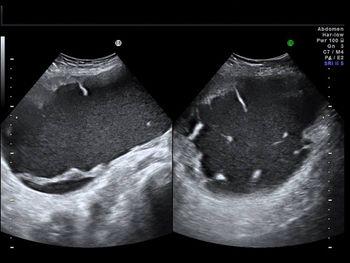

A 40-year-old woman reports a 20-week history of amenorrhea. What is your diagnosis based on these images?